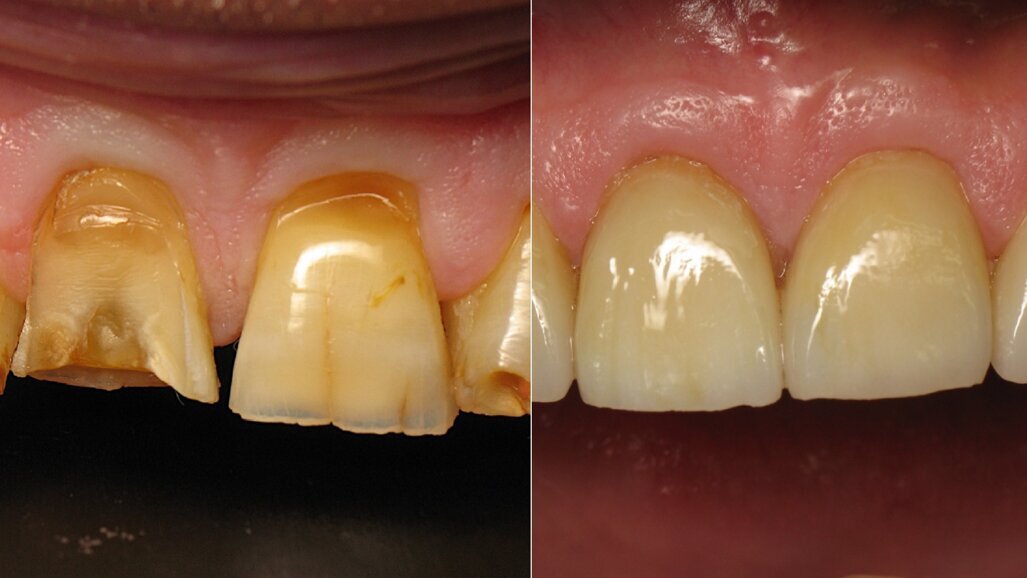

Figure 1 shows a clinical situation in which the patient will be able to smile literally and figuratively. The teeth have a harmonious shape, position and shade, despite minor defects such as cervical lesions of the mandibular incisors. There is also good periodontal health, there being no plaque or gingivitis. What the reader is far from suspecting is that this final situation corresponds to the placement of four crowns on teeth #12–22.

Figure 2 shows us close up the quality of the restorations and the care taken by the dental technician in the production of these crowns. Indeed, the anatomy is harmonious and leaves no black triangles at the gingival papillae. In addition, the shade is natural, saturation increasing gradually from the incisal edge to the cervical region. The laboratory technician added a subtle touch of ochre stain in vertical lines. Particular attention has been paid to this clinical case for a result that exceeded the patient’s expectations.

Fig. 11: Initial situation.

Fig. 12: Close-up of the initial situation.

Captured at the same time as Figure 10, Figures 11 and 12 show the initial situation of this patient, who came for a consultation to rehabilitate his maxillary incisors. The diagnosis revealed nocturnal bruxism as the origin of several areas of crown destruction: wear of the incisal edge, abfraction, missing restorations, cracks and a complex coronary fracture. It is easy to understand why the choice of material was zirconia. It is also easy to understand the motivations of this patient to recover his lost smile. This degradation over time is inevitable, but in this patient, it was particularly fast and aggressive. Reversing the course of time was therefore obvious in restoring the dental health of this patient.